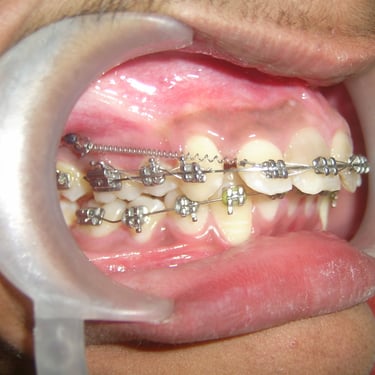

Orthodontics & Dentofacial Orthopaedics

Fix metal braces Self ligating braces Ceramic braces Colored braces Aligners/Invisalign Lingual braces TMJ disorders Cleft lip and palate patients Head gear Face mask Chin cup Ortho mini implants/TAD Essix retainer Fix lingual retainer Functional appliances Twin block appliance Removable ortho